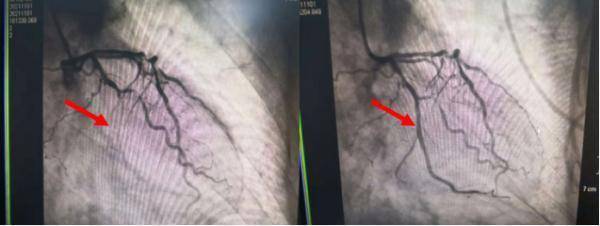

患者马先生今年30岁 , 平时身体良好 。 但马先生的工作需要其长期上夜班 , 同时 , 他还有大量吸烟的习惯 。 在连续两个晚上加班熬夜后 , 突发胸闷、胸痛 , 于是前往苏州高新区人民医院就诊 。

急诊手术时 , 医生发现其心脏一支大血管99%狭窄 。 在置入一枚支架后 , 马先生临床症状得到缓解 , 目前情况稳定 。

文章图片

左:术前 右:术后

图源:苏州高新区人民医院心血管内科